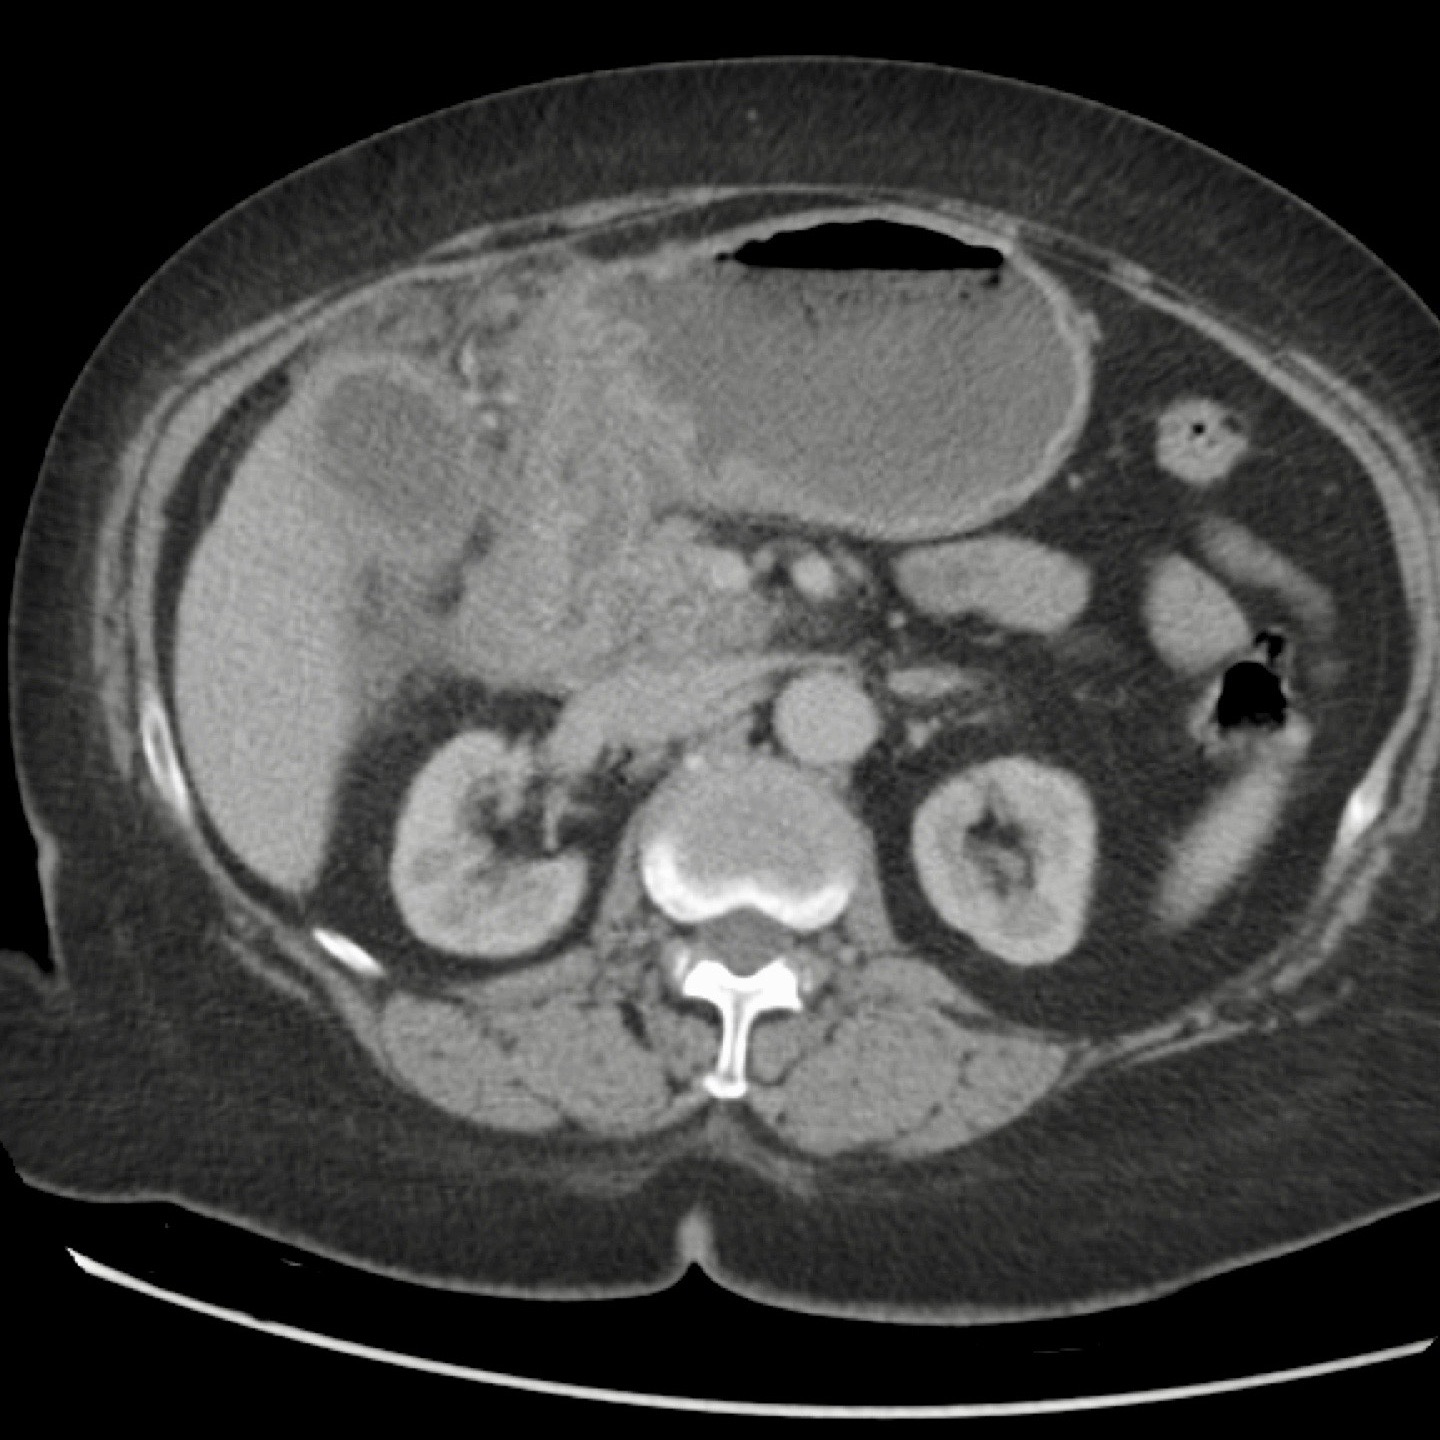

Đây là bệnh nhân có tình trạng ứ đọng dạ dày từng đợt và CRP thấp.

Một viên sỏi lớn bị “kẹt” trong đường rò từ túi mật biến dạng đến tá tràng.

Dày thành tá tràng thứ phát (đầu mũi tên) cùng mô viêm và mô xơ xung quanh gây ra tình trạng ứ đọng dạ dày từng đợt kèm nôn mửa.

Hình ảnh của một bệnh nhân nữ cao tuổi, nhập viện vì ứ đọng dạ dày và nôn mửa.

CRP là 55, nhưng được ghi nhận là 160 vài ngày trước đó.

Siêu âm cho thấy một viên sỏi lớn trong túi mật chứa đầy chất lắng cặn, thành túi mật không đều.

Dạ dày giãn to và có dày thành tá tràng đáng kể (đầu mũi tên) kèm viêm xung quanh (dấu hoa thị).

Nội soi dạ dày được thực hiện do nghi ngờ ác tính, nhưng sinh thiết chỉ cho thấy hình ảnh viêm.

Tiếp tục xem CT.

CT xác nhận chẩn đoán hội chứng Bouveret.

Dẫn lưu túi mật qua da đã giải quyết các triệu chứng ứ đọng dạ dày.

Một năm sau, viên sỏi dường như đã tự di chuyển vào lòng tá tràng, và bệnh nhân phát triển tắc ruột do sỏi mật điển hình, được phẫu thuật thành công.